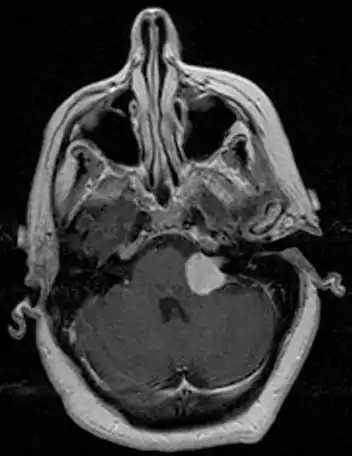

![]() | |

| Bilateral schwannomas in a patient with neurofibromatosis 2 | |

For the most part, unilateral sporadic vestibular schwannomas are readily treated successfully by modern medical techniques. Having bilateral VSs is a more troublesome condition. Bilateralism is considered to be the hallmark and main diagnostic criterion of Neurofibromatosis Type II (NF2), a genetic disorder that is heritable, progressive, difficult to manage, and has a 1 in 2 chance of being passed on to each offspring. NF2 patients tend to have a more severe mutation, although there are mild mosaic cases in which only some cells carry the mutation. Genetic testing confirming mutation of the NF2 gene is recommended. About 50% of people with NF2 have a de novo mutation, and about 50% of these new mutations will be mild mosaic cases which are less likely to be passed on. NF2 patients may develop other cranial and spine tumors. NF2 develops during the teens or early adulthood, whereas sporadic VSs are diagnosed mostly in patients between the ages of 40–60 years. Both varieties of VS (sporadic and NF2) are very rare, accounting for only about 8% of all primary brain tumors. The incidence of NF2 is approximately 1 per 60,000 people.[6][7][8]